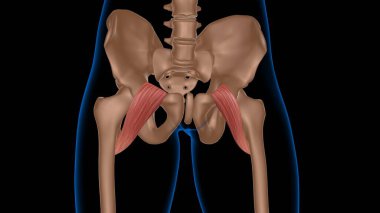

Tıbbi konsept 3 boyutlu illüstrasyon için insan kadın kas anatomisi

KasBileşenlerDorsalfleksörPalmarbrachiiBrevisLongusabdüktöradductorekstansiyonOrasına3d oluşturma3B illüstrasyonCarpiteresdeltoideusDigitorumbrachioradialiskomplikasyondigitiquintipollicisprofundusulnarispronatorPalmarisinterosseiopponenscoracobrachialisKas Anatomisilongus muscleinterossei musclebrevis musclelummbrical muscletricep mucslepollicis musclesuperficialis muscleBenzer İçerikler